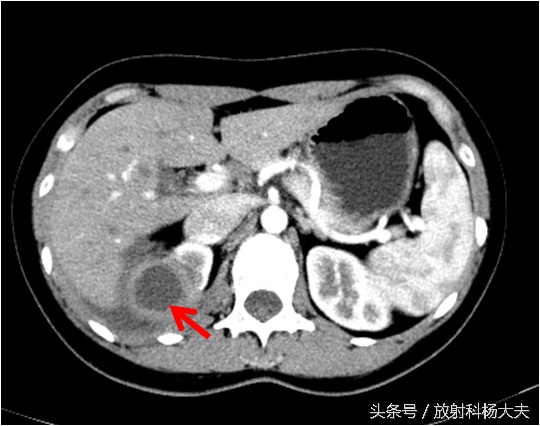

骨科接着开了腰椎CT,骨科大夫怀疑背部是一个窦道,猜测窦道可能是脊柱旁,因此开了腰椎CT平扫,腰椎CT扫描的时候是以腰椎和椎间盘为主的,范围不大,但我们却在不大的范围内发现了问题,除了窦道,肾上有东西!但腰椎CT平扫实在难以评价,因此做了腹部增强CT,发现了实属罕见的情况:那个确实是个窦道,如下图红箭所示,窦道外口在体表,也就是流水的地方。窦道的上口却是在肾脏!

如下图,右肾上长了个东西,囊性的,壁挺厚。